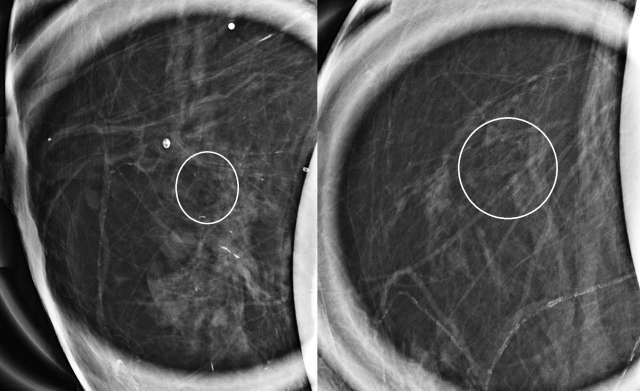

The mammographic appearance of ADH is usually that of grouped or regional calcifications, most often of the amorphous or coarse heterogeneous subtype. ADH can also be less commonly present as a mass or focal asymmetry on screening mammograms. As calcifications are the most common presentation of ADH on screening mammograms, and as ultrasound suboptimally evaluates areas of calcification, ADH is less often seen on ultrasound examinations. However, the most common sonographic feature of lesions demonstrating ADH on ultrasound-guided biopsies includes a hypoechoic, microlobulated mass without acoustic transmission or shadowing. The most common appearance of ADH on breast MRI is nonmass enhancement in a focal, linear, segmental, or regional distribution. The second-most common appearance is that of an enhancing mass.